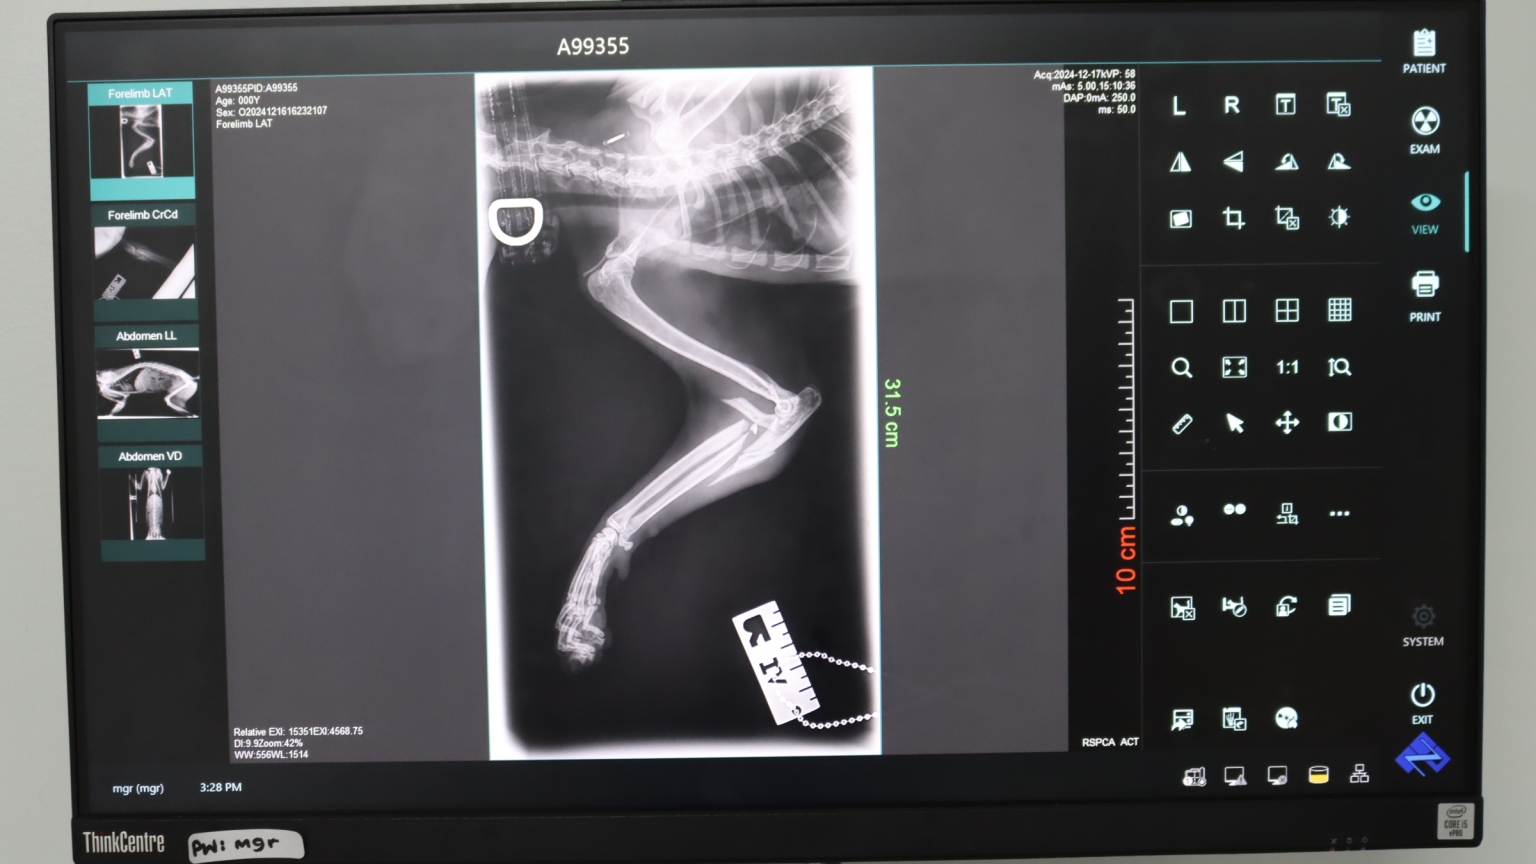

You were there for Kumo, a gentle stray with a severely broken leg.

Kumo